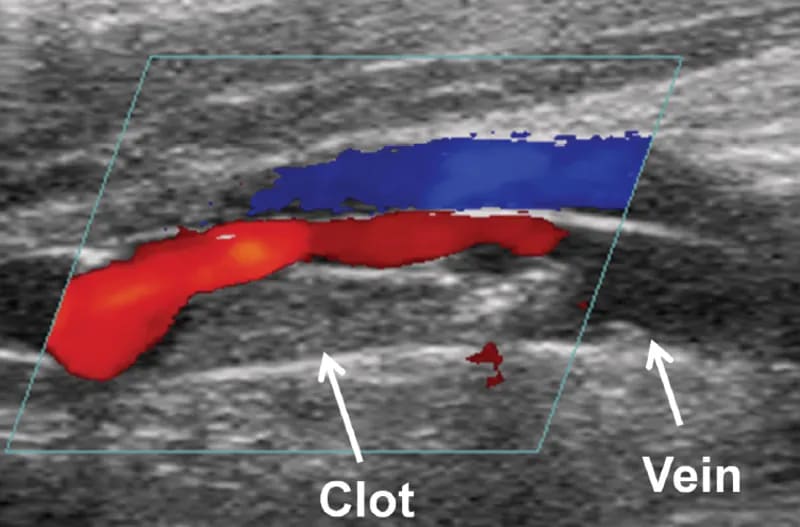

A Deep Vein Thrombosis (DVT) Doppler Ultrasound is a special type of ultrasound which is used to measure blood flow through the upper limb veins as well as the deep leg veins and assess any blockage to blood flow such as a blood clot. DVT commonly occurs in calf veins, and occasionally in those of the thigh.

When isolated in the leg veins, DVT can result in pain, skin inflammation and ulceration. However, if the clot breaks off and travels through the bloodstream into the lungs, it is known as pulmonary embolus which can be life-threatening.